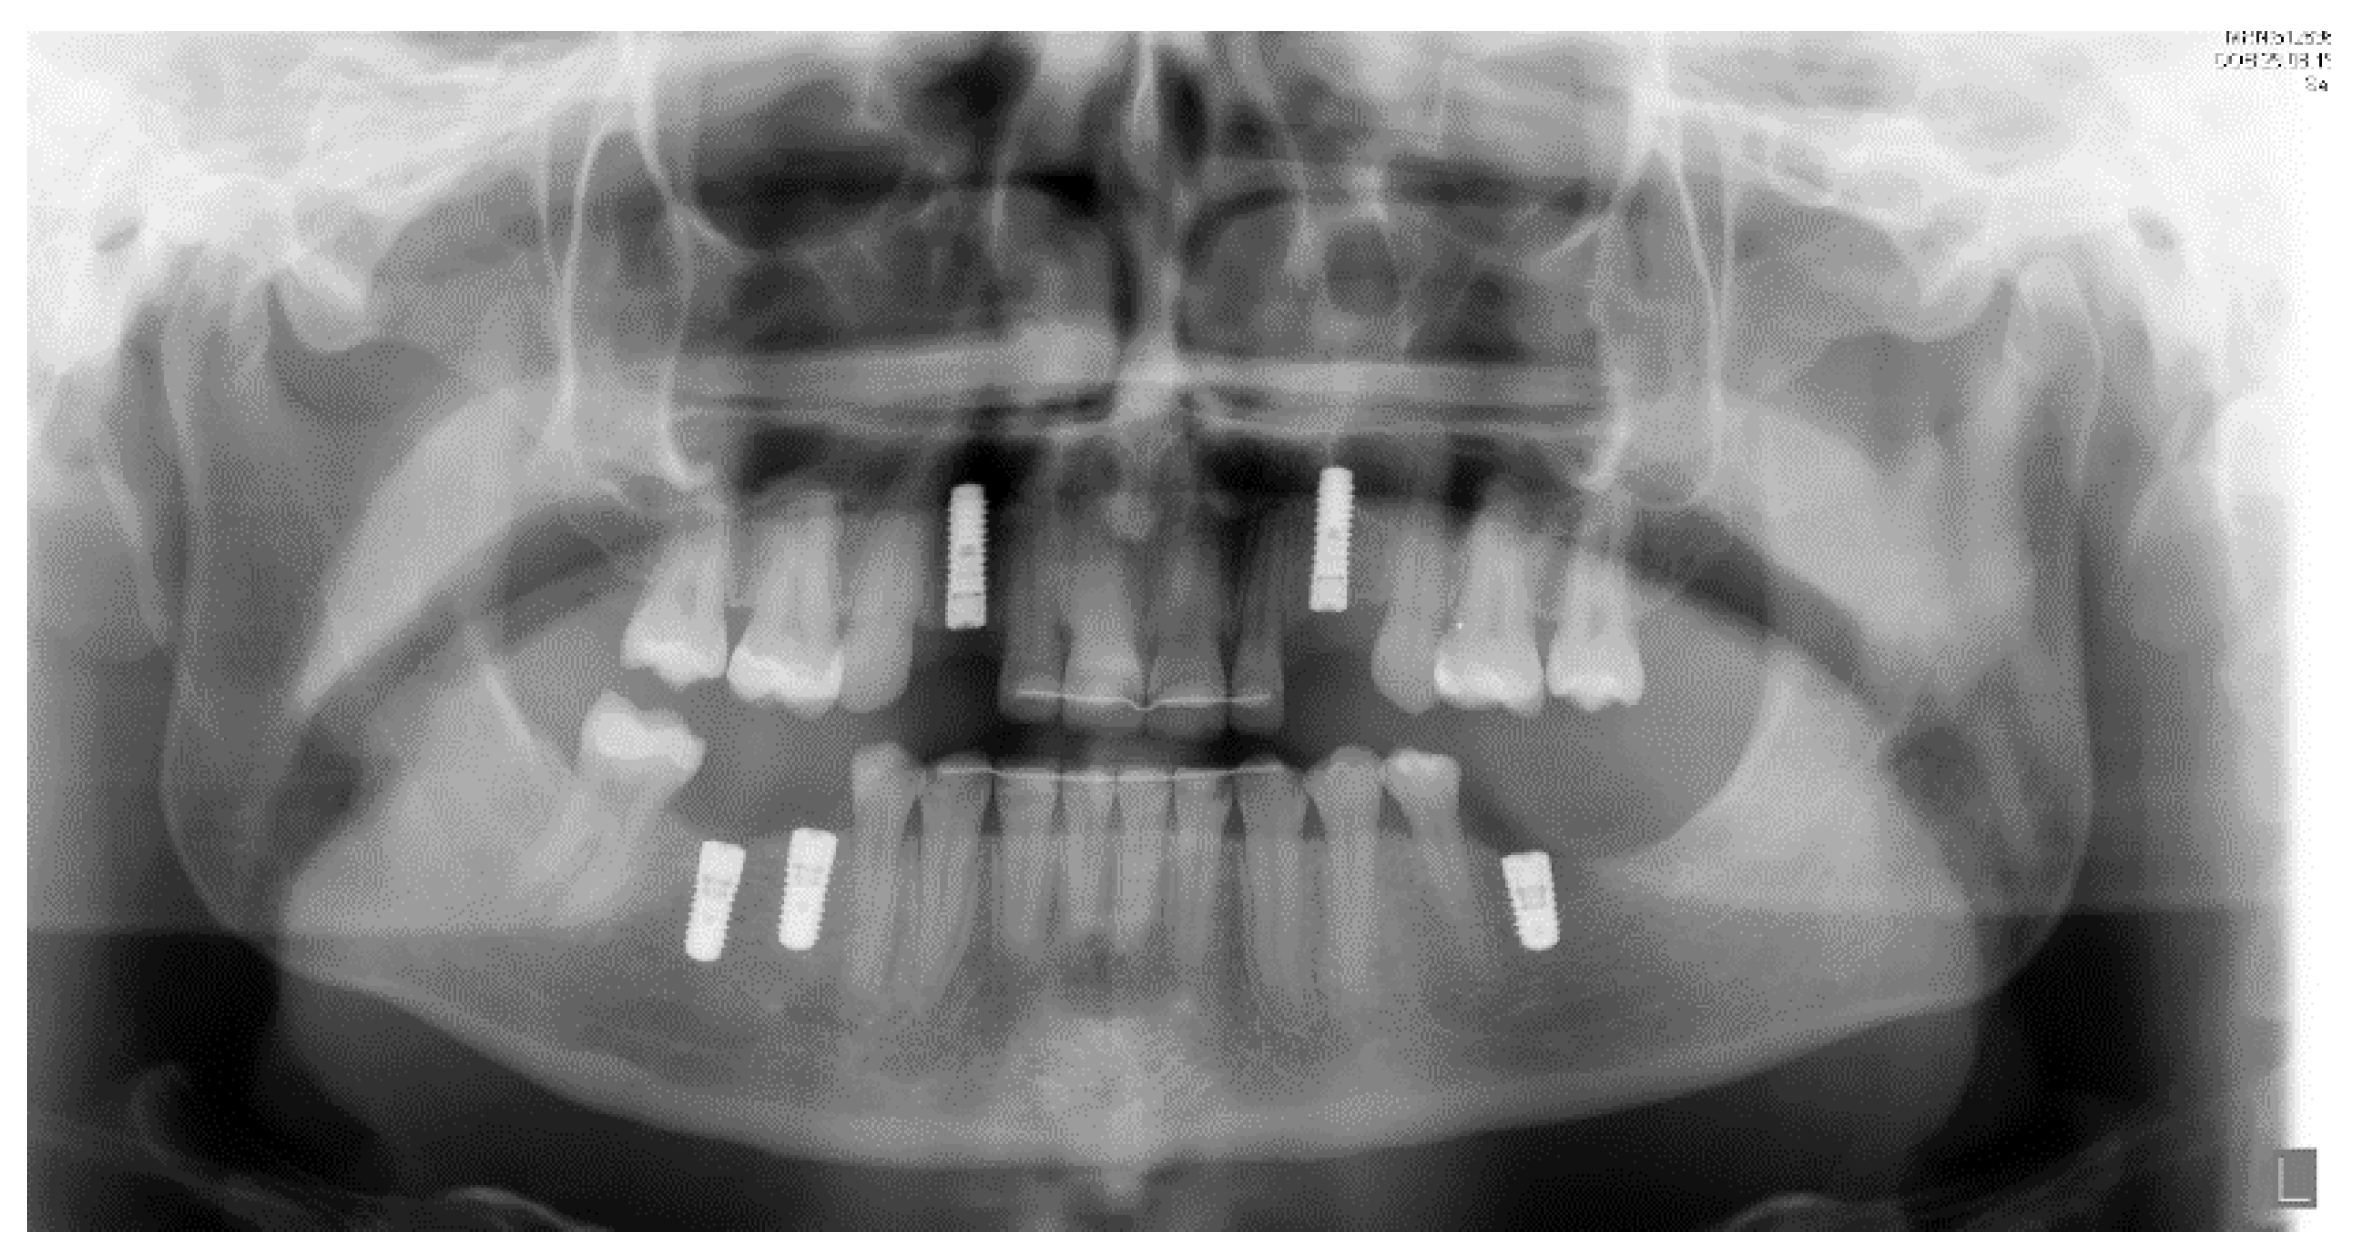

Figure 10.

Post-operative panoramic radiography.

Titanium dental implants (Bone Level, 3.33 × 12 mm and 4.1 × 8–10 mm, Straumann, Basel, Switzerland) were placed under local anesthesia (Septanest 1:200,000) at sites 13, 23, 36, 45, 46, using the surgical guide as reference. After a healing period of three months, implant-supported porcelain crowns were installed with a torque strength of 35 Ncm. Additionally, teeth 13 and 23 were prepared for a crown with shape of premolar teeth, and porcelain crowns were cemented using resin cement (RelyX, 3M, Neuss, Germany). The treatment showed satisfactory aesthetic and functional results at 1-year follow-up. Dental implants were osseo-integrated without marginal bone loss (Figure 10 and Figure 11).